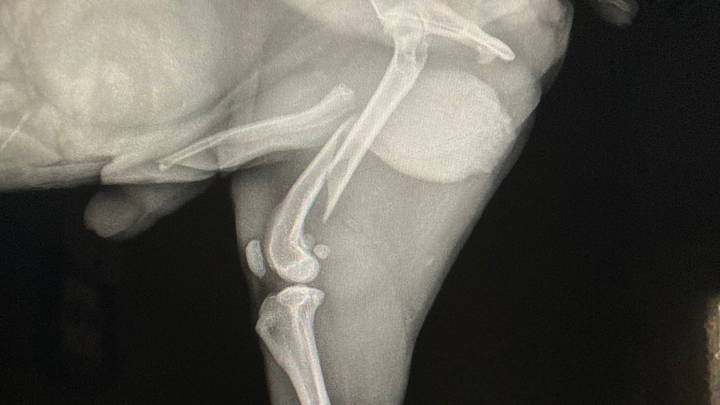

Update: 3:25a.m. Roscoe has a broken femur. His thigh is swollen and he’s given pain meds for now. Will need to take him to specialty hospital for a board certified surgeon evaluation in just a few hours. I’m told cost for surgery is between $8000 to $10,000, not including other miscellaneous fees. Either that I’m told to amputate his leg to save money. Seriously?!!! I’m all out of tears. I refuse to have his leg amputated because I don’t have the funds.

He lost his footing and fell today while he was on the couch and landed on his right hip. While we wait in the emergency room, he is whimpering in pain. His leg is bent the wrong way and I’m afraid to move it. He yelps when I tried to straighten it.